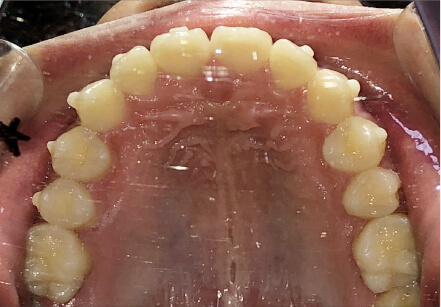

9歳

/

男性

相談内容

ガタガタしているのが気になる

カウンセリング・診断結果

叢生。上3.3スペース不足。耳鼻科紹介

治療内容・方法

全額アライナー矯正

術後の経過・現在の様子

リンガルアーチ使用

治療のリスク

痛み・歯根吸収・歯肉退縮・虫歯・後戻り

費用・治療期間

140,800円、1年1ヶ月